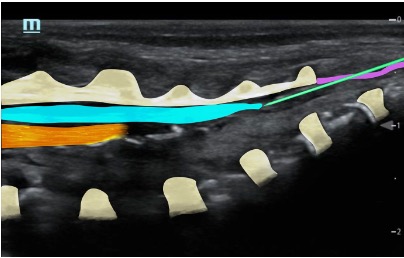

Needle insertion at the apex of the sacral hiatus at an angle of 45⁰ until resistance

Reangle to 30⁰ and insert another 5mm (advance under US vision) – characteristic pop through ligament

Perform saline test à Confirm position (saline expands the epidural space and pushes the dura more anteriorly)

Track the LA spread by sliding the probe cranially (probe positioned paramedian longitudinally); ensure the appropriate level is reached for the intended operation